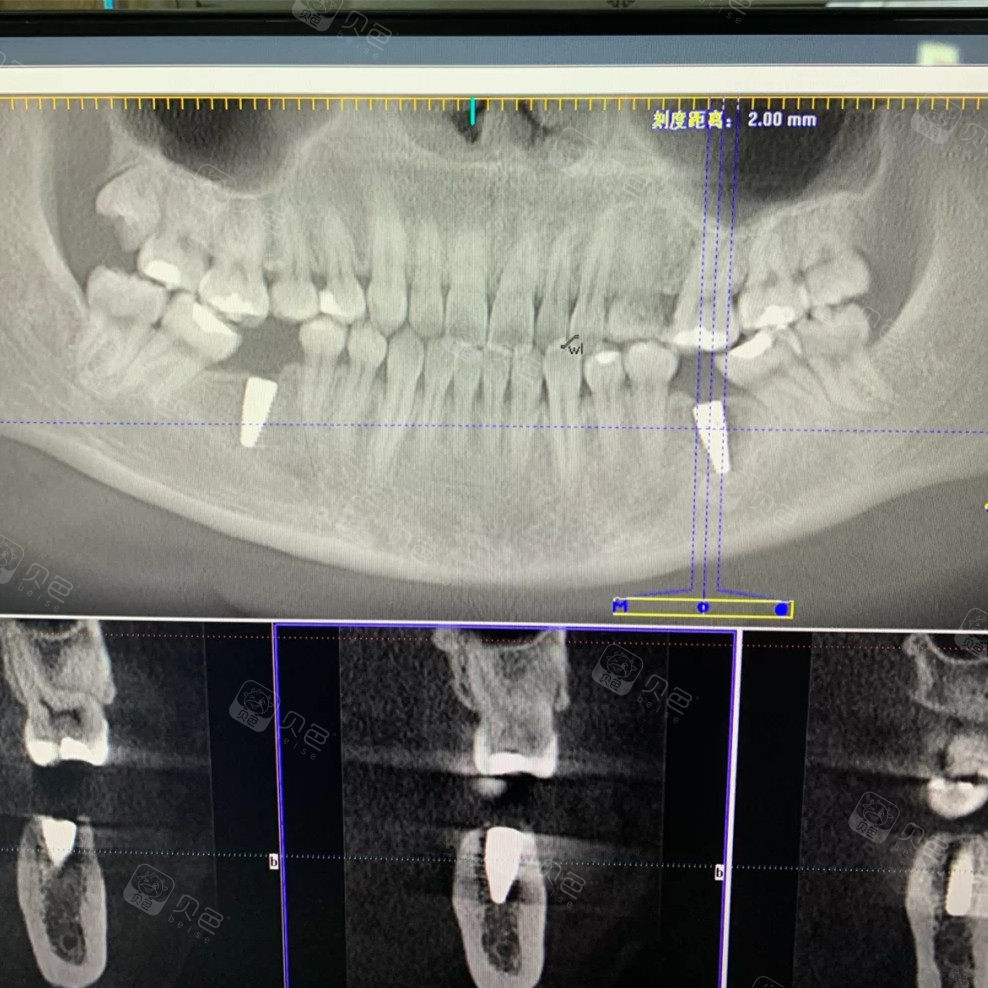

我第二次的牙片

图片尺寸1080x538